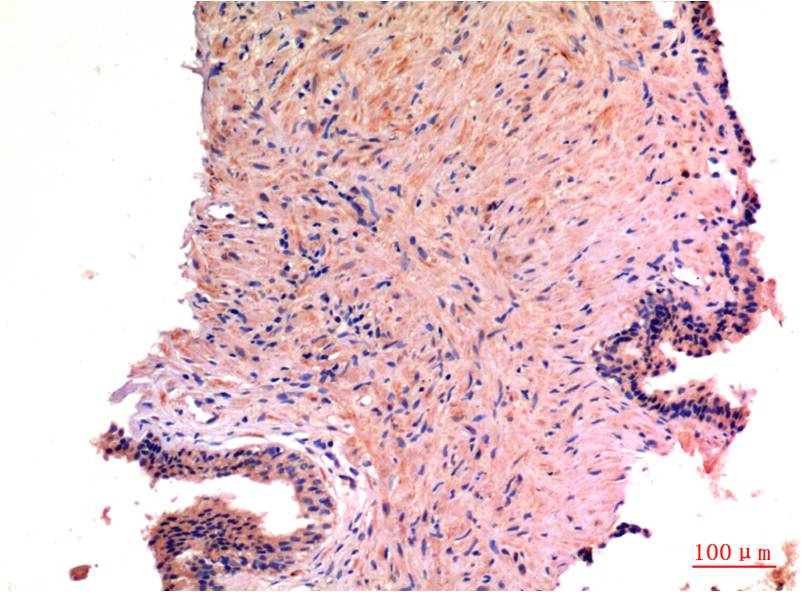

Immunohistochemistry analysis of paraffin-embedded Human Prostate Carcinoma Tissue using LC3A antibody. High-pressure and temperature Sodium Citrate pH 6.0 was used for antigen retrieval.